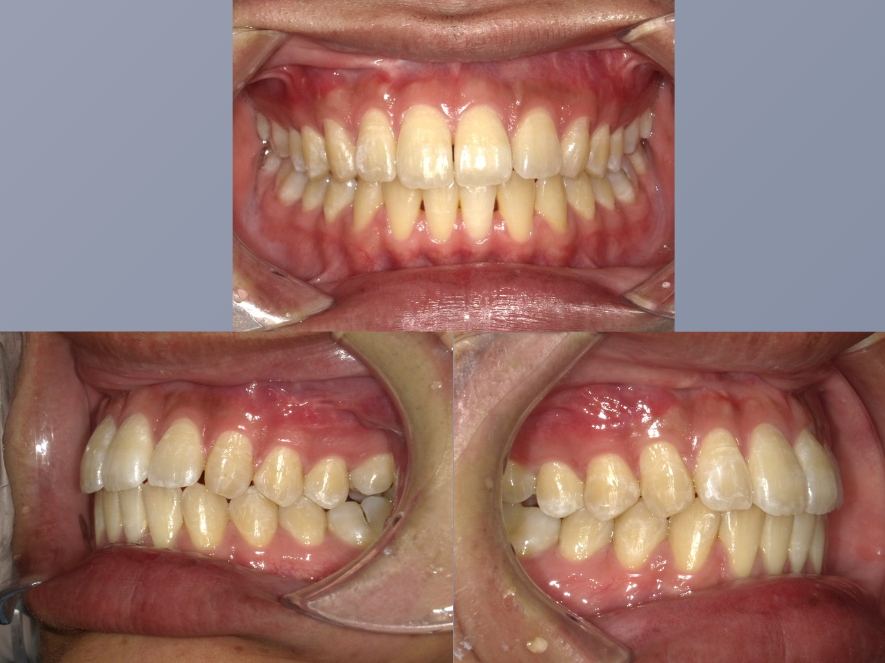

治療前

| 年齢・性別 | 20代・男性 |

|---|---|

| 主訴 | インビザラインが気になる。 |

| 期間 | 1年9カ月 |

| 費用 | 495,000円 |